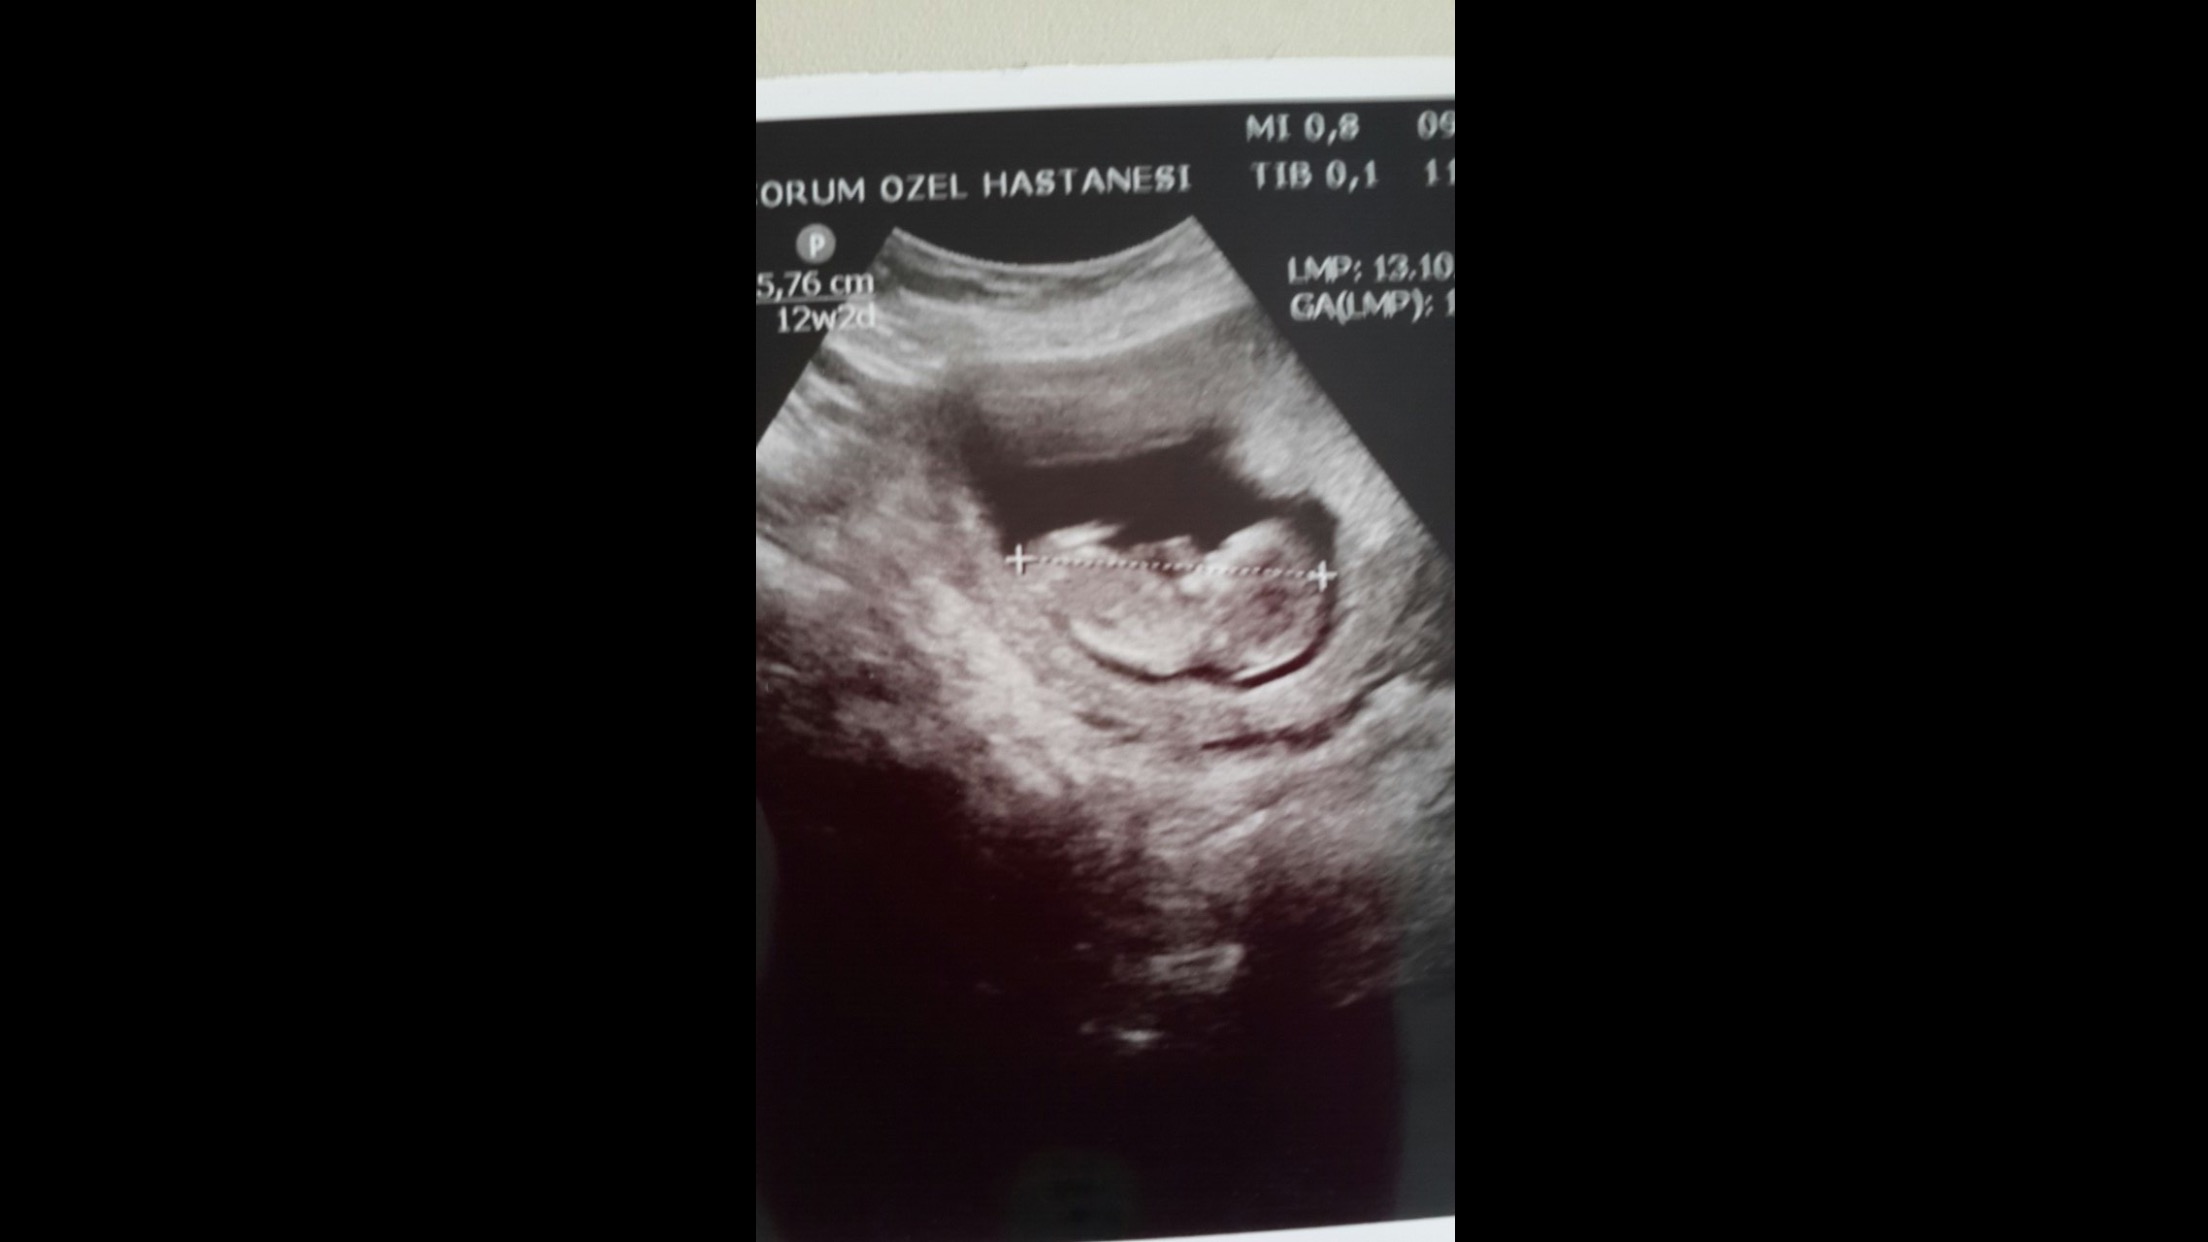

1 1xyz1 Yeni Üye Üye 10 Ocak 2017 #130 Merhaba, fotoğraflardan cinsiyet anlaşılıyor mu? Doktor kız gibi görünüyor dedi. Ekli dosyalar 2.jpg 1,4 MB · Görüntüleme: 608